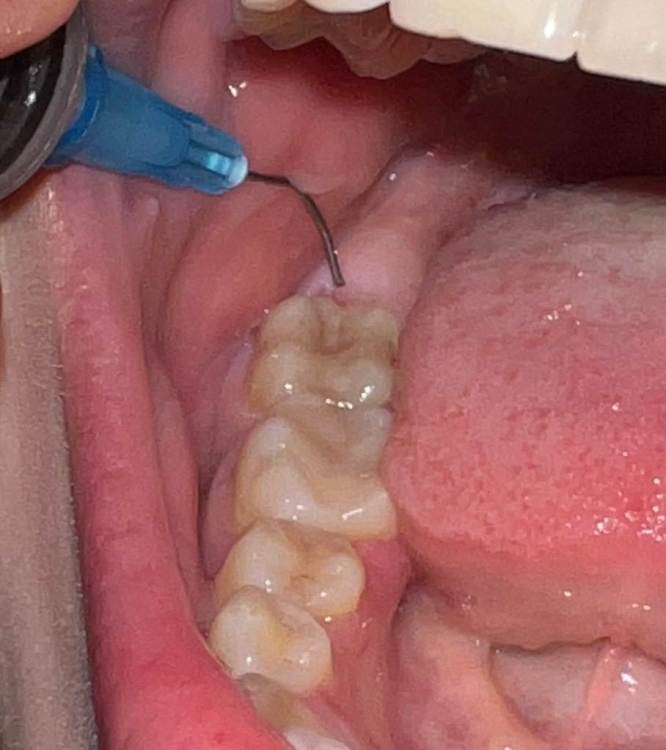

Karina21 Опубликовано 28 декабря, 2021 Автор Поделиться Опубликовано 28 декабря, 2021 @Bier @Марья Моревна @Irouil @Женька и снова здравствуйте! Полгода назад я удаляла зуб мудрости, был альвеолит, вылечили ежедневными промываниями на протяжении недели у врача, потом промывать сказали самостоятельно дома до заживления. И лунка все еще не заросла до конца, я попыталась сфотографировать сколько еще пространства есть(насколько иголка может опуститься в лунку) но плохо получилось. Эта дырочка на стыке с седьмым зубом, иногда чувствую в этом месте небольшой дискомфорт(я не знаю, может это как фантомные боли и я просто себя накручиваю?)там наверняка скапливаются бактерии несмотря на промывание,но почистить же я там не могу щеткой от налета,подскажите пожалуйста, не повредит ли это 7 зубу и насколько долго вообще может заживать эта лунка(мне говорили она будет заживать изнутри) Заранее спасибо за ответ! Ссылка на комментарий